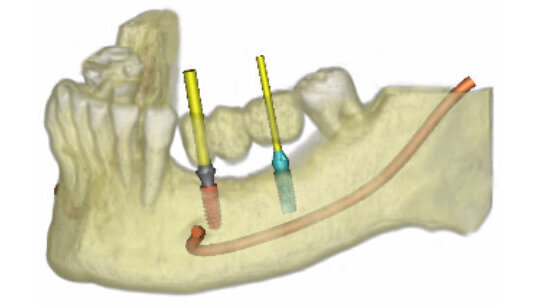

Panoramica di impianti, abutment compatibili e soluzioni SurgiGuide®

Trovare un impianto in una libreria che conta oltre 8000 impianti di 90 case implantari potrebbe sembrare come cercare un ago in un pagliaio. Non con SimPlant® 2011!La libreria degli impianti è stata concepita per mostrare immediatamente ai medici ciò che stanno cercando:

• Selezionare la propria soluzione SurgiGuide® preferita per risparmiare tempo sia in fase di pianificazione che in fase di ordine

• Risparmiare tempo scegliendo contemporaneamente impianto e abutment

• Soddisfare specifici requisiti protesici partendo da un abutment; vengono infatti mostrati solo gli impianti compatibili con quell’abutment

Visualizzazione 3D istantanea

Gli utilizzatori di SimPlant® Pro possono iniziare a pianificare senza dover effettuare la segmentazione, riducendo quindi il tempo da dedicare ad ogni caso. Questa è una delle nuove funzioni avanzate di rendering del volume che combina una straordinaria visualizzazione con un notevole risparmio di tempo.

La segmentazione è più rapida grazie all’anteprima 3D istantanea. È possibile creare immagini 3D di alta qualità che mostrino le radici dei denti, arcata antagonista e soluzioni protesiche in minor tempo. SimPlant® 2011 dispone degli strumenti migliori che esistano. Segmentazione o no, SimPlant® è ciò che fa per voi.